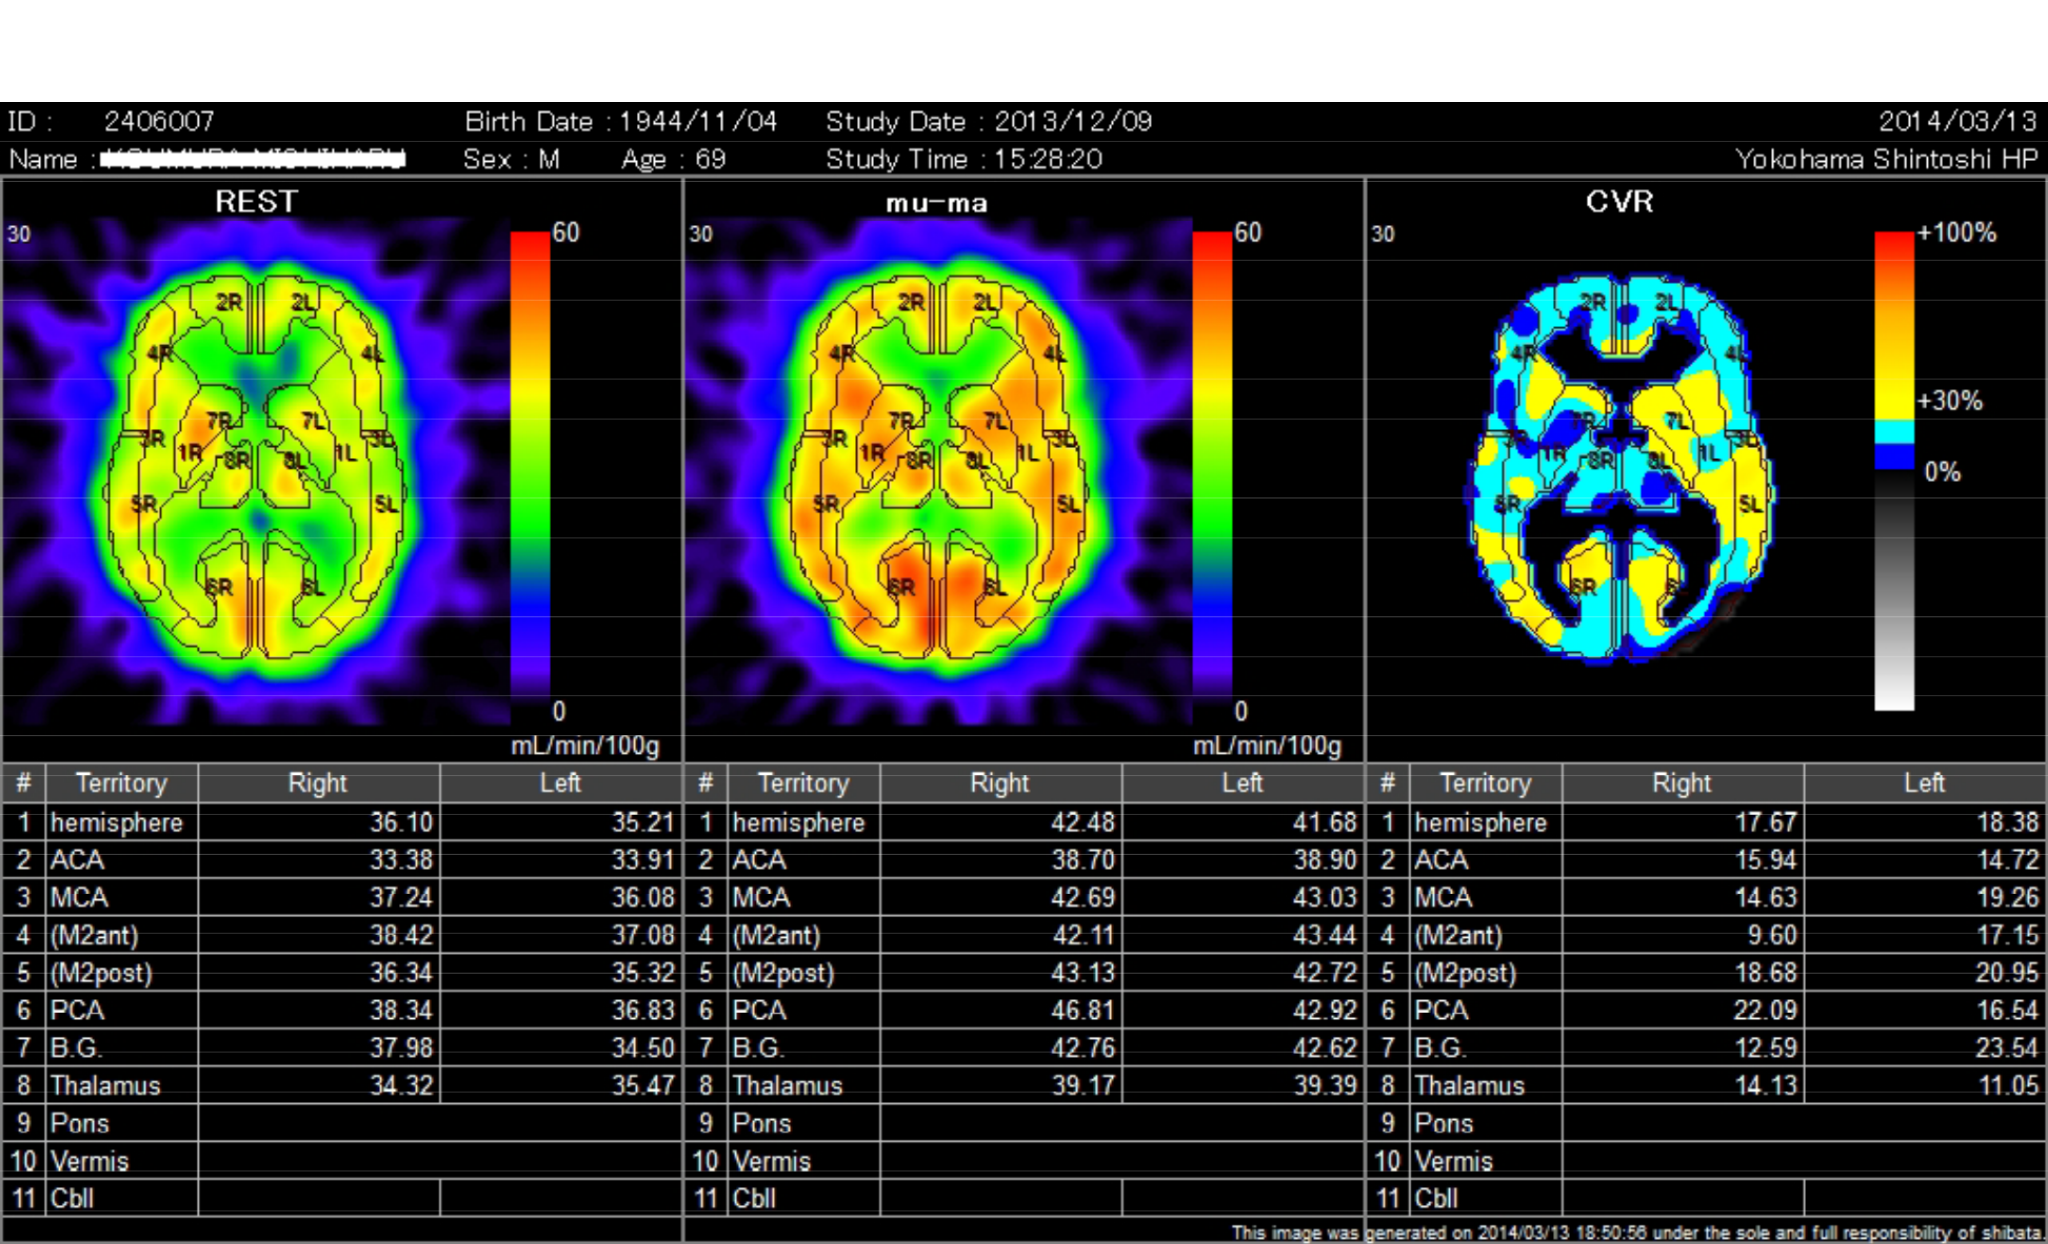

【画像】

経頭蓋微弱超音波振動刺激装置による刺激前後における脳内血流の SPECT

画像

被験者(68歳、男性)

出典:2015 年9月

日本補完代替医療学会誌第 12

巻第 2 号